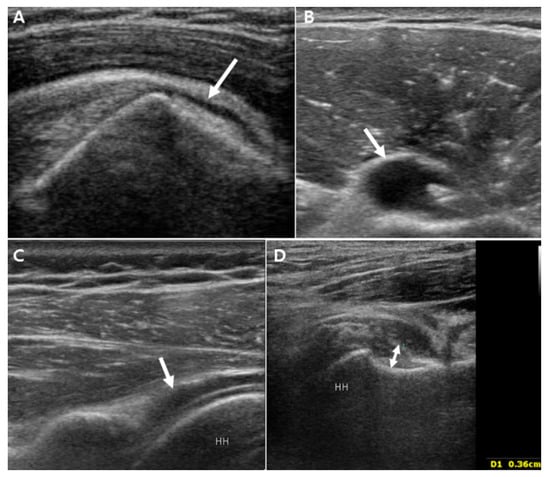

3.2.1. Unilateral Shoulder US Findings in PMR Patients and Bilateral FS Patients

3.2.2. Comparison of Bilaterality of Abnormal Shoulder US Findings in PMR Patients and Bilateral FS Patients